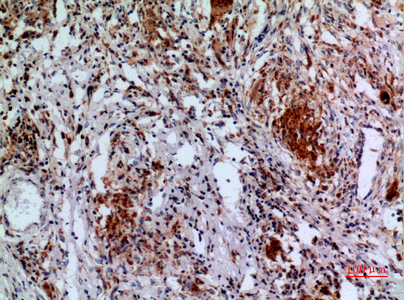

![APAF1 antibody [C3], C-term detects APAF1 protein at cytoplasm in rat liver by immunohistochemical analysis. Sample: Paraffin-embedded rat liver. APAF1 antibody [C3], C-term (GTX101067) diluted at 1:400.

Antigen Retrieval: Citrate buffer, pH 6.0, 15 min](https://www.genetex.com/upload/website/prouct_img/normal/GTX101067/GTX101067_40359_20160713_IHC-P_R_w_23060100_579.webp)